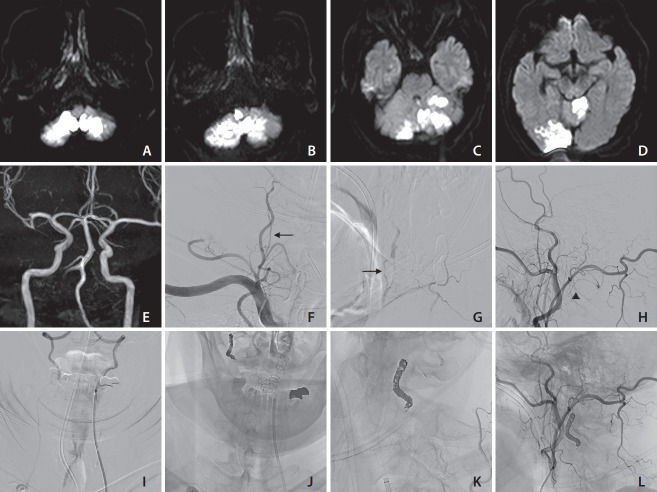

Vertebral artery stump syndrome (VASS) is a rare condition that can cause posterior circulation ischemic stroke due to occlusion of the ipsilateral vertebral artery (VA) orifice, resulting in blood flow stagnation and embolus formation. Although there is no established treatment for this condition, we observed 3 cases of VASS out of 326 acute ischemic stroke cases at a single institution from April 2021 to October 2022. Despite the best possible antithrombotic treatment, all 3 patients had recurrent ischemic strokes. One patient underwent drug-eluting stenting of the VA orifice to relieve occlusive flow. The other 2 patients received coil embolization, which resulted in the disappearance of their culprit collateral flow. None of the patients had recurrent ischemic strokes after endovascular intervention. Based on our observations, stenting and coil embolization are effective methods for preventing future recurrences of VASS.

Abstract Image